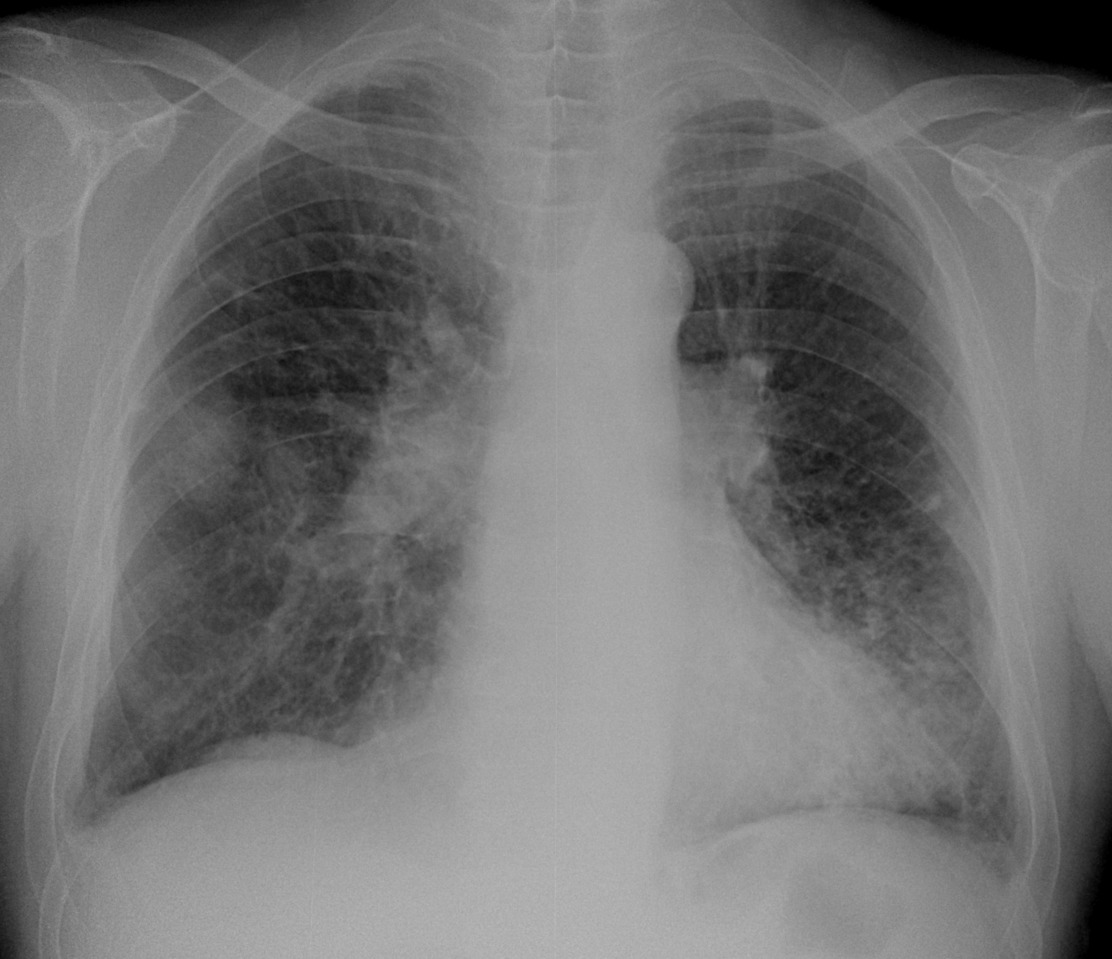

Случай 2.  М, 79 лет. ИБС, ГБ, обостение бронхита. Сейчас жалобы на подъем температуры до 38,4 кашель со слизисто-гнойной мокротой. Что скажете на счет него? Мне не нравится "мазня" с обеих сторон в нижних отделах, больше слева, правый корень и тень справа. Онкология может. Снимки на сегодня:

По второму - пневмонию в S6 справа пишем (онко - в уме). Рентген контроль после противовоспалительного лечения.

№2. Надо онко исключать.

А слева мазня и раньше была, и она не прогрессирует. Условия съёмки разные. Я расцениваю  эту картину, как остаточные явления ранее перенесенной пневмонии в S 9 слева.

Во втором случае расширенные, но в целом структурные корни, на боковом снимке кругление в корнях скорее всего за счет расширенной легочной артерии, инфильтраты в легких - в целом укладывается в картину застоя, после лечения можно посмотреть динамику в легких